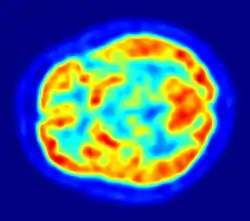

PET scan of the human brain

PET imaging with oxygen-15 indirectly measures blood flow to the brain. In this method, increased radioactivity signal indicates increased blood flow which is assumed to correlate with increased brain activity. Because of its 2-minute half-life, oxygen-15 must be piped directly from a medical cyclotron for such uses, which is difficult.[16]

PET imaging with FDG takes advantage of the fact that the brain is normally a rapid user of glucose. Standard FDG PET of the brain measures regional glucose use and can be used in neuropathological diagnosis.